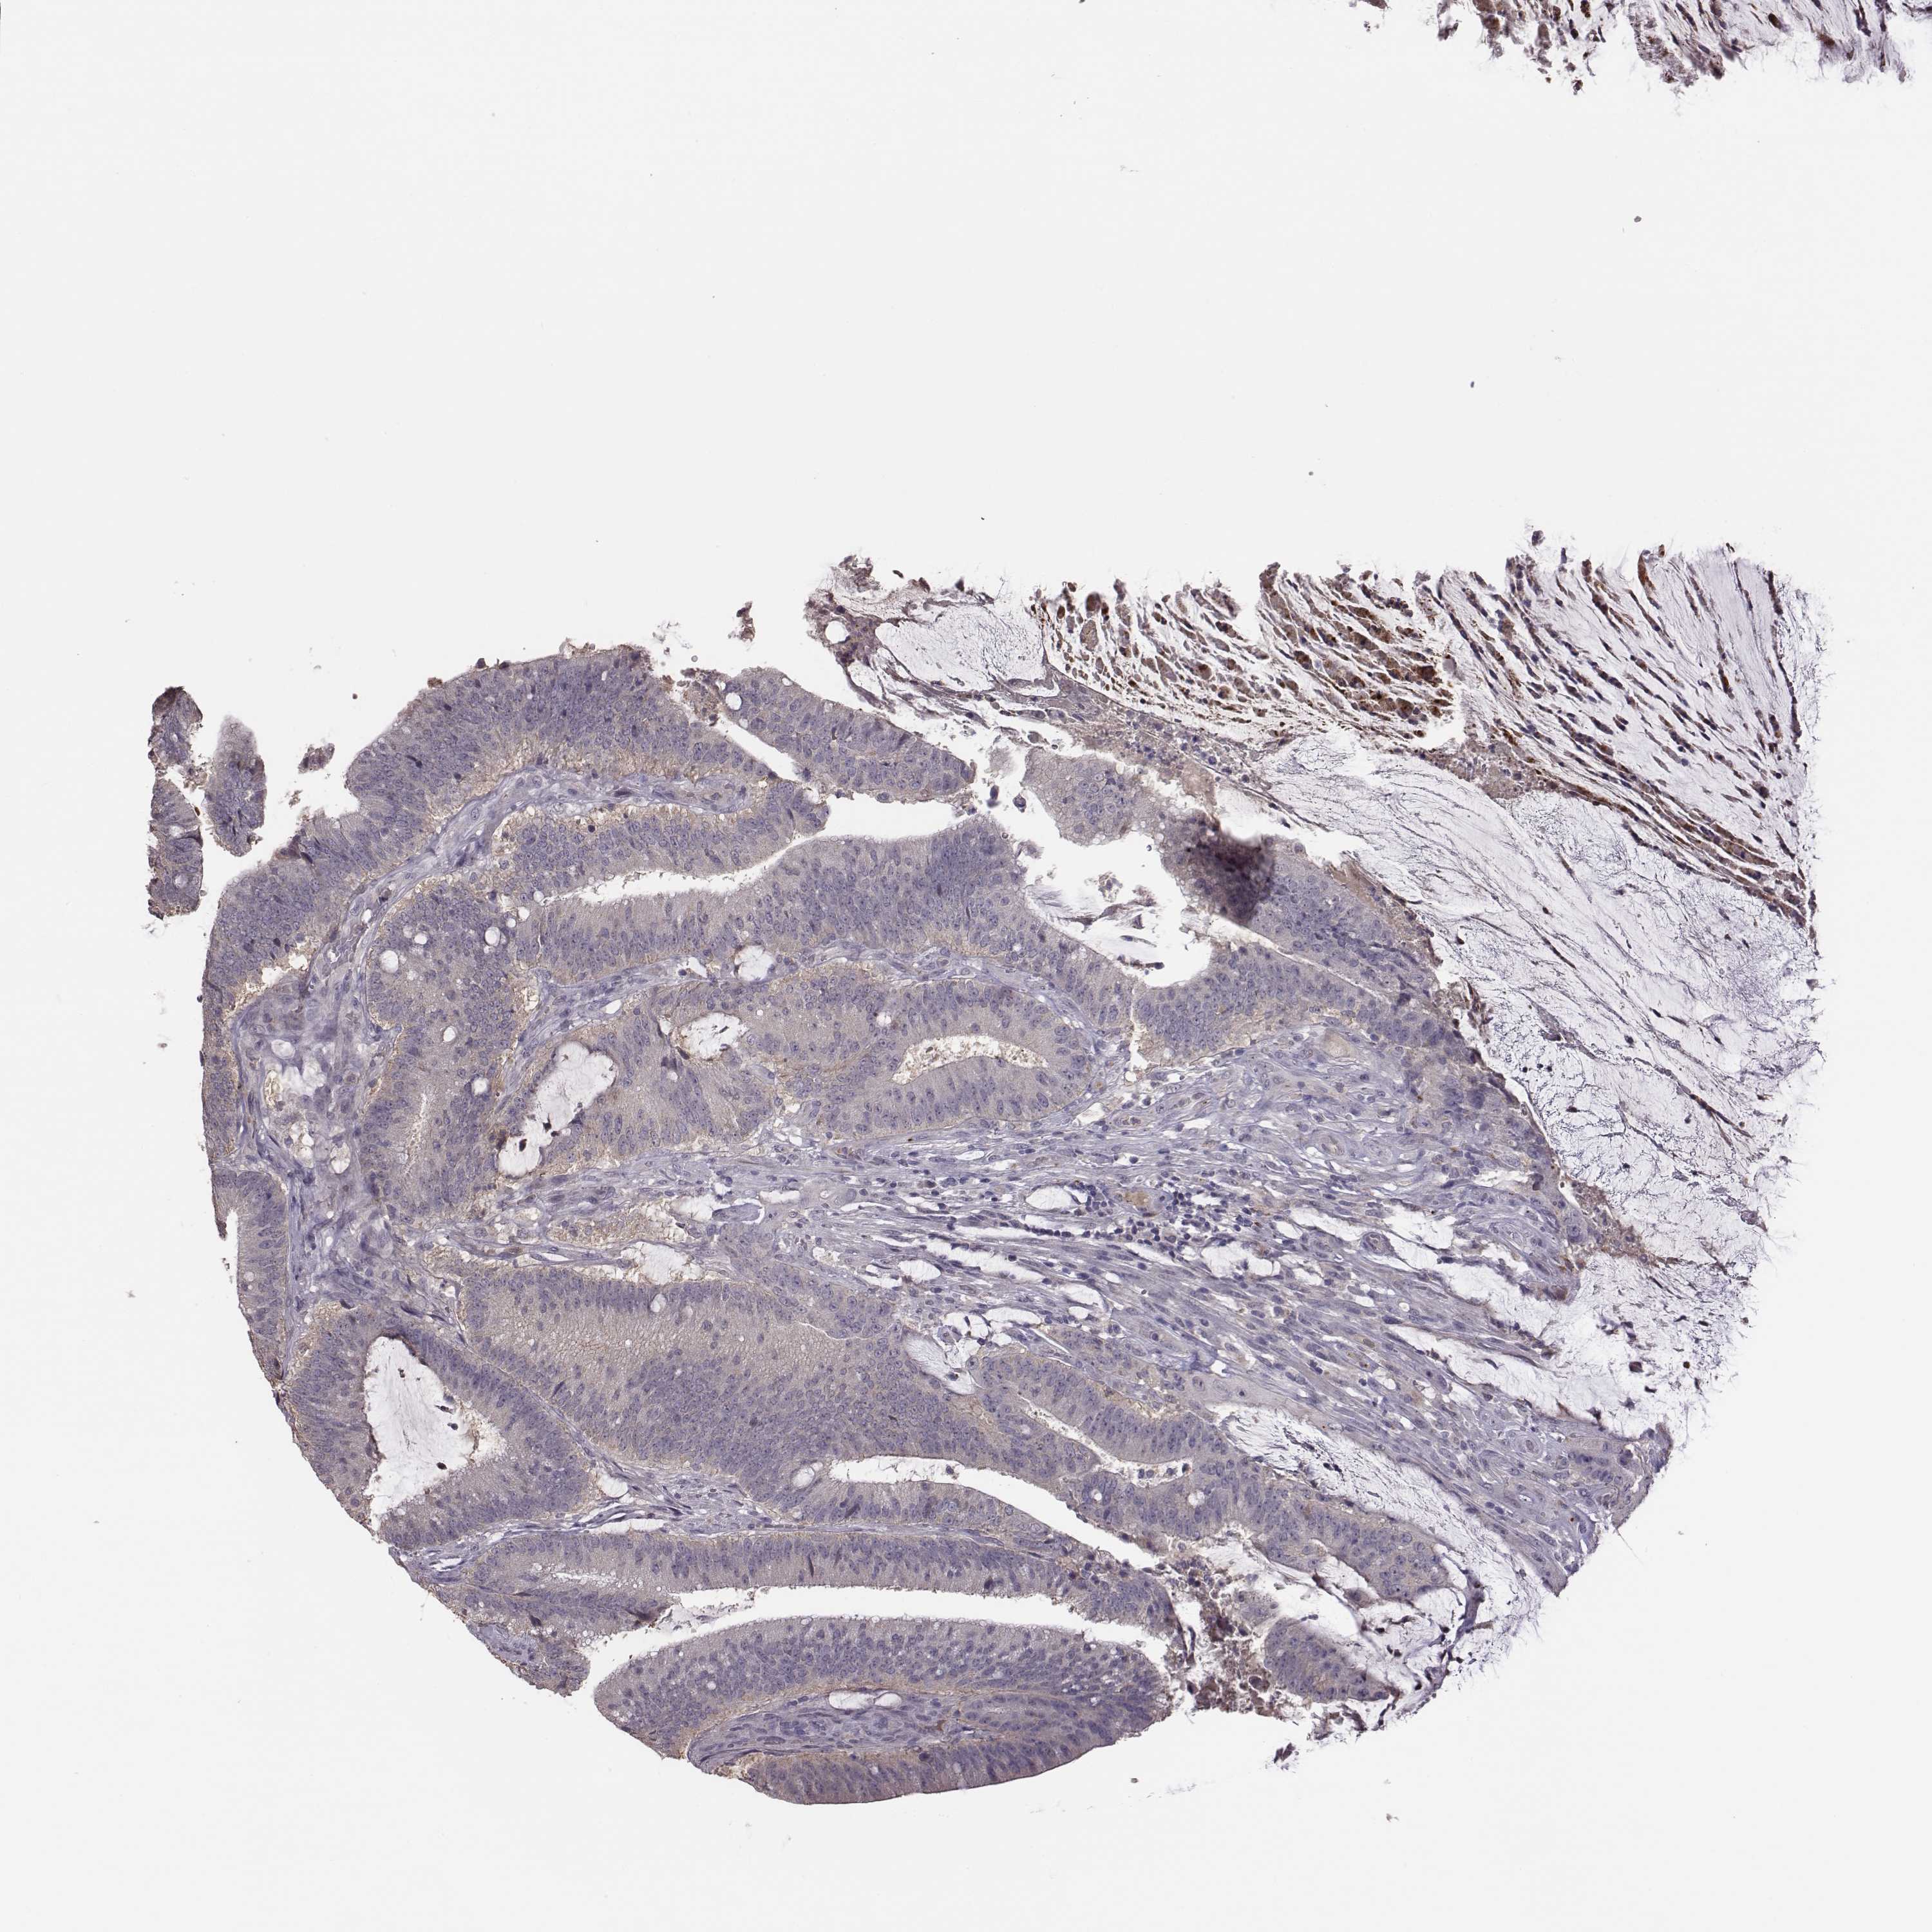

CANCER COLORECTAL CANCER Show tissue menu

ANTIBODIES

AND

VALIDATION

Colorectal cancer

Human cancer